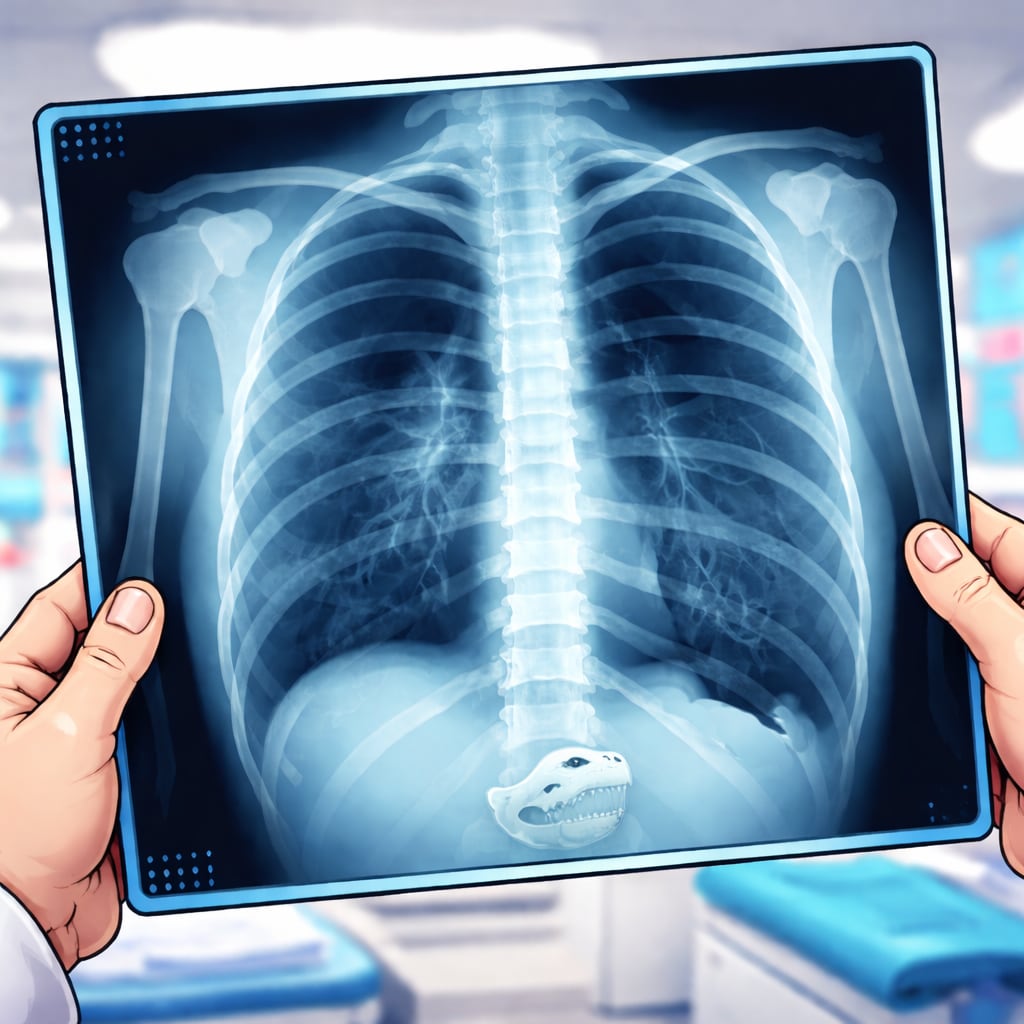

This is one of the most common questions we get—and the answer is yes. At Watkinsville Urgent Care, we offer on-site digital X-ray, so you don’t have to travel to another facility or wait days for answers.

X-rays are an important tool in urgent care and are commonly used to evaluate persistent coughs, possible pneumonia, bone fractures, joint injuries, and certain sprains or dislocations. Having X-ray available in-house allows us to quickly confirm or rule out serious conditions and move forward with the right treatment plan during your visit.

One key difference between our clinic and some urgent care centers is how our X-rays are interpreted. Every X-ray performed at our clinic is over-read by a board-certified radiologist. While our providers review images in real time to guide your care, a radiologist—whose specialty is reading imaging studies—also reviews the films to provide an additional layer of expertise and safety. Not all clinics with X-ray capability use radiologist over-reads.

This approach helps reduce missed findings, improves diagnostic accuracy, and ensures you receive the same level of imaging oversight you would expect from a hospital or imaging center—without the long waits or added costs. If further evaluation or follow-up is needed, we’ll contact you and help coordinate next steps.

If you’re dealing with an injury, chest symptoms, or another condition where imaging might be helpful, our team is ready to help. Having on-site X-ray with expert review means faster answers, fewer delays, and peace of mind—all in one visit.